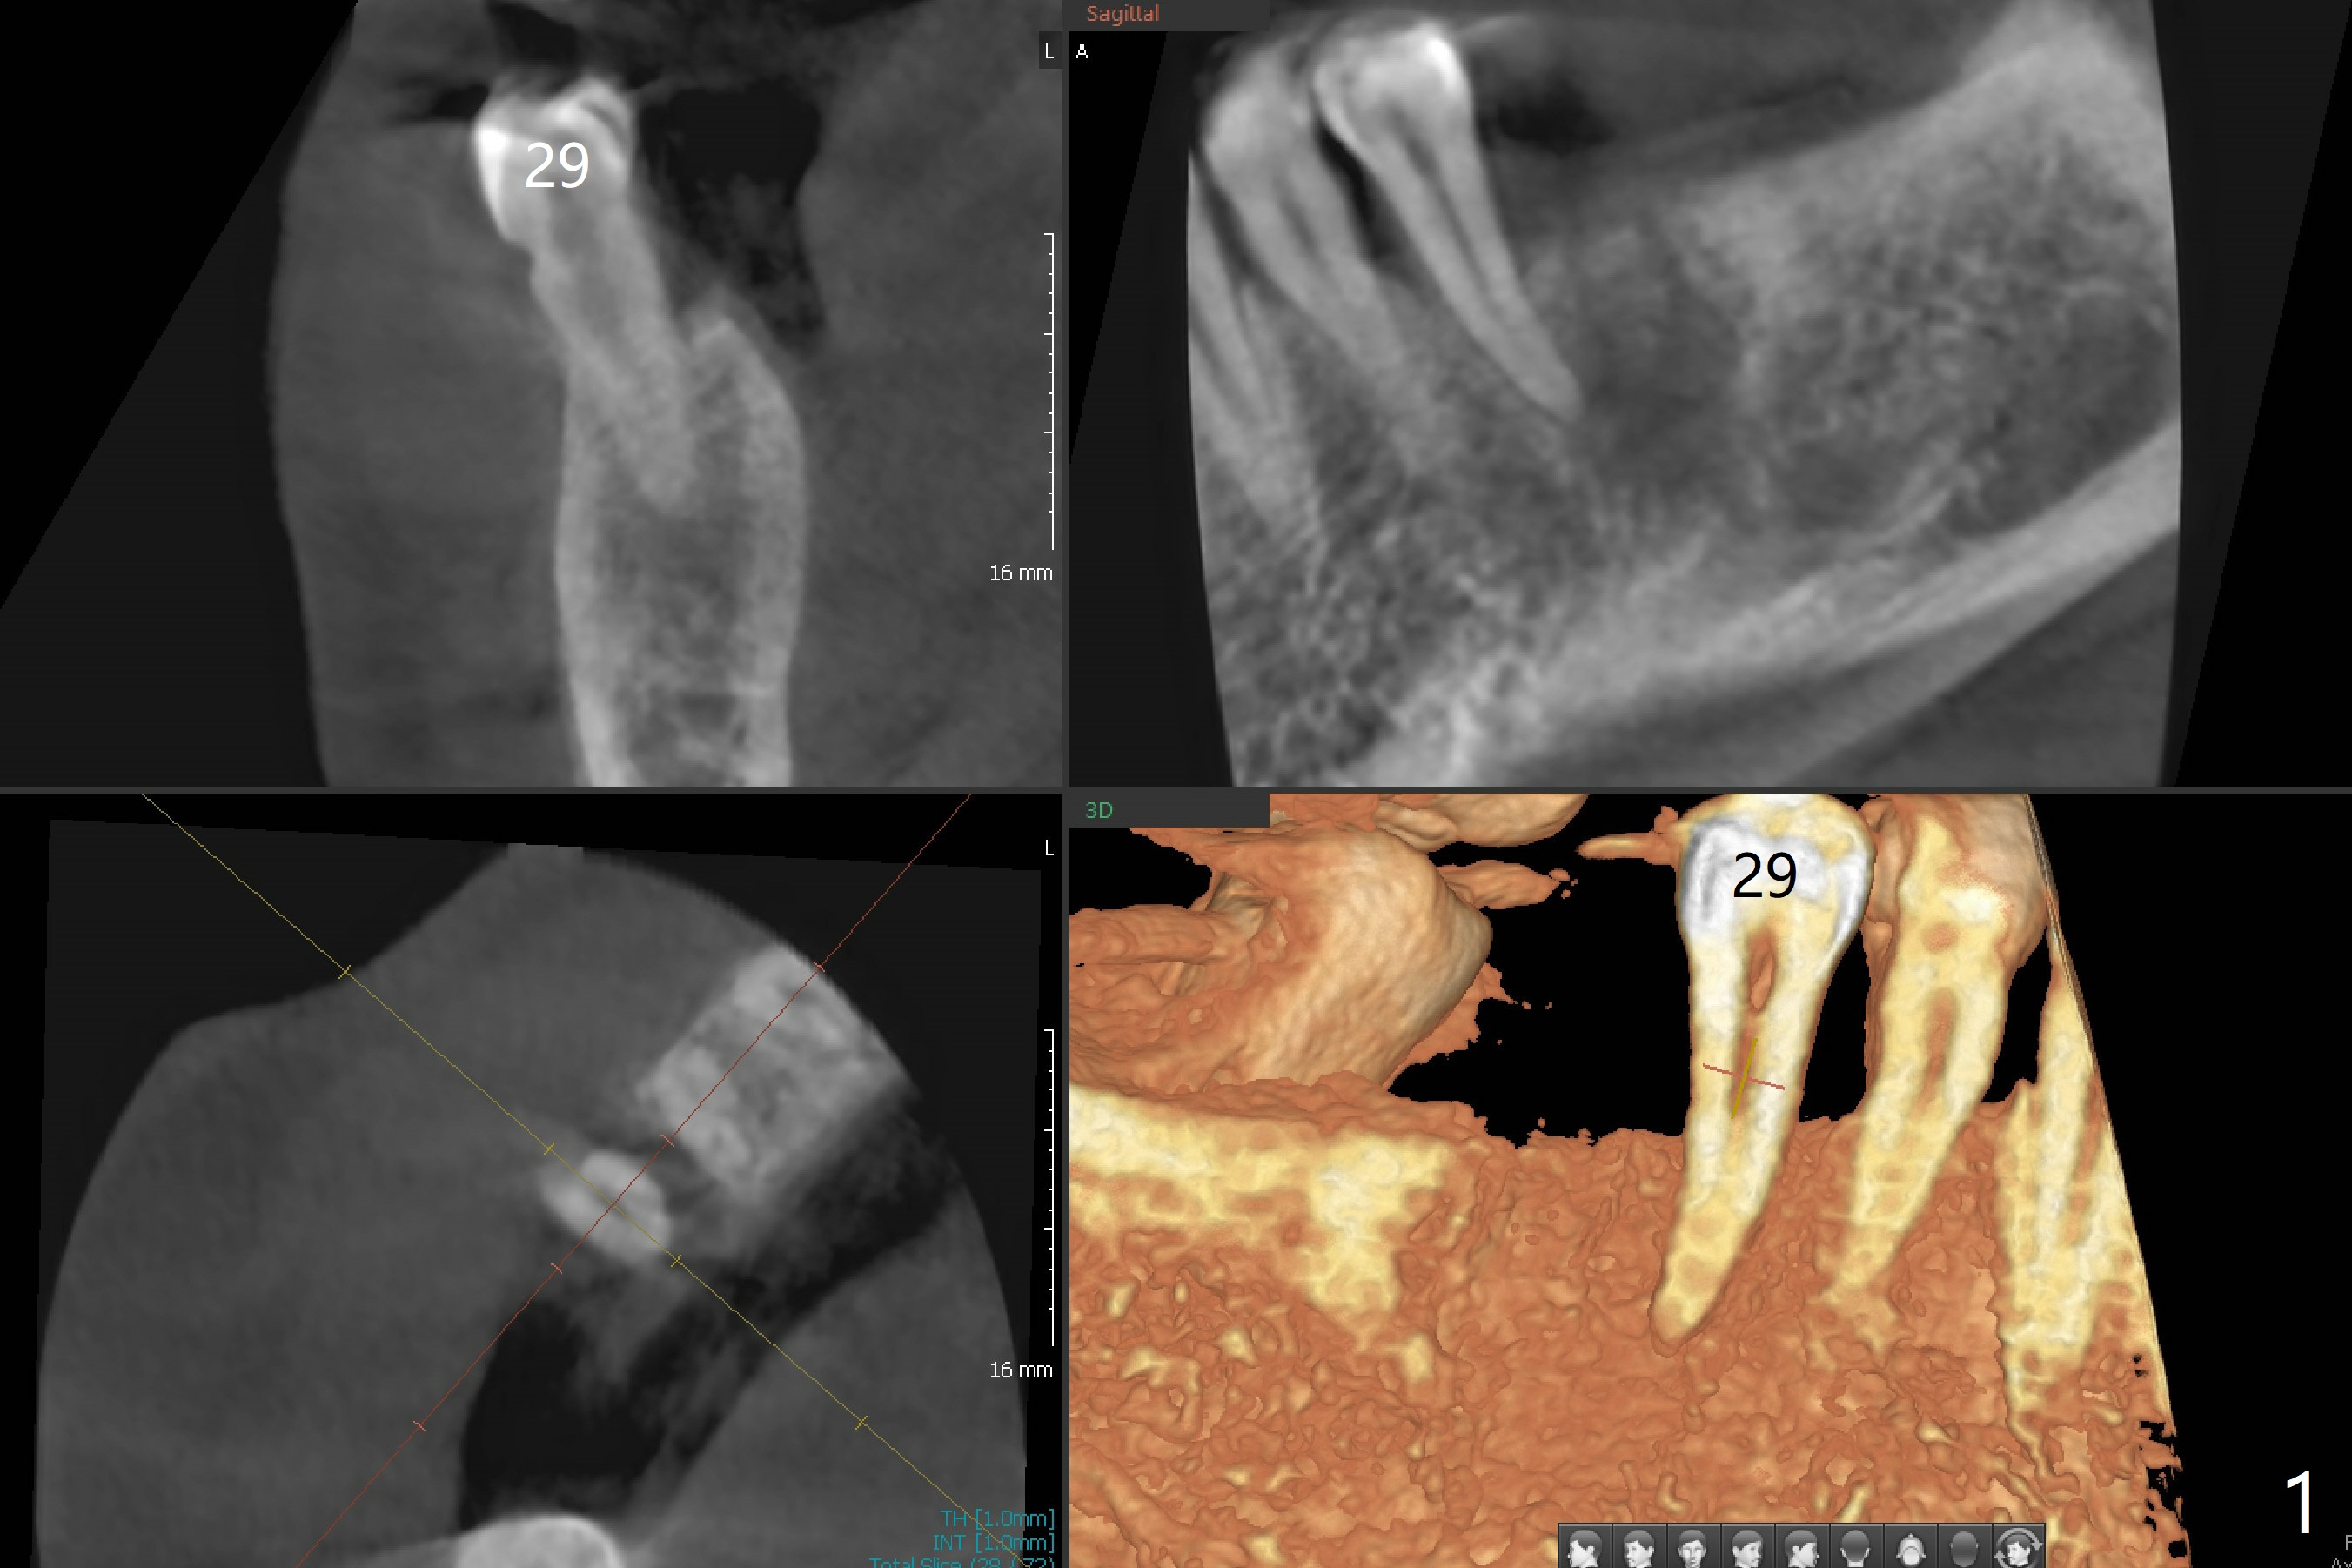

Minimal bone loss is observed 4 months postop (Fig.4).